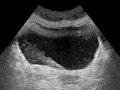

- Ultrasound showing a jet of urine entering the bladder (large black section) through the ureter